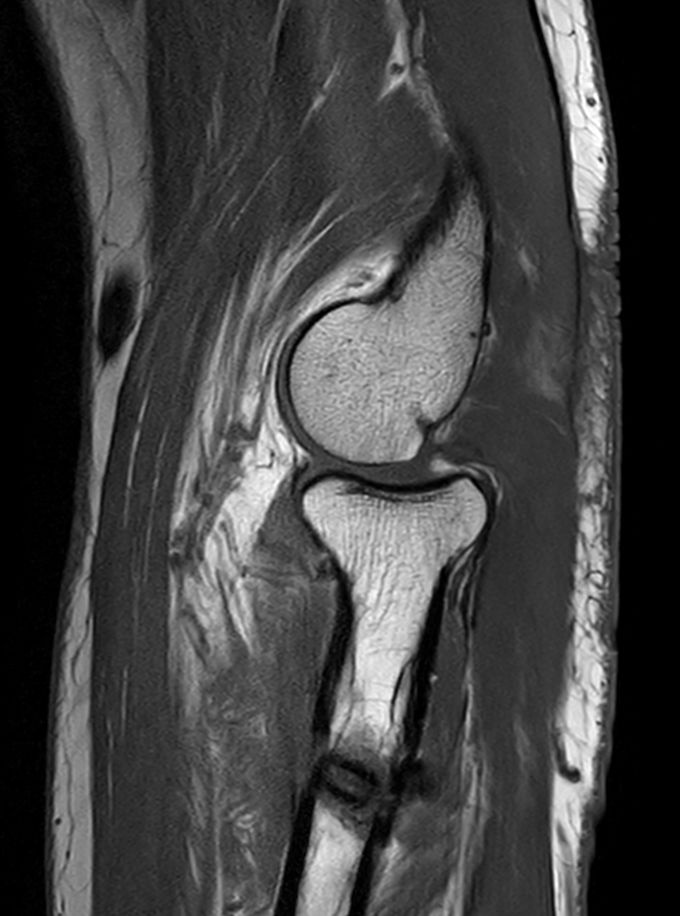

Routine Elbow

Routine imaging of the Elbow with the dS Small Extremity 8ch coil. MultiVane XD is used to deliver high resolution diagnostic images even in the case of patient motion. Compressed is used to speed up the entire exam with virtually equal image quality1.

T1w TSE Compressed SENSE